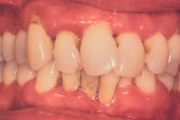

- igemed veritsevad (19)

- igemed punetavad (21)

- ige on paistes (mädapunn)

- igemed on tursunud/vohavad (17)

- igemepiir on taandunud (3)